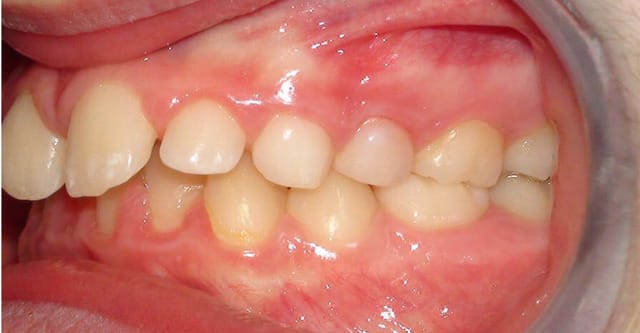

Je vous joins également pour faire plaisir à certains des photos intra-buccales bien qu'elles n'apportent absolument rien de plus.

si, si, si, classe d'angle, ddm, supraclusion, volume des arcades, etc...

OK, on voit une supraclusie incisives, mais pas de DDM et j'en aurais parlé dès le départ si ça avait pu apporter quelque chose au plan de traitement.

Et on voit aussi la vestibuloversion de la 22 qui est effectivement un signe positif d'inclusion vestibulaire de la canine. Dans ce sens, tu as raison.